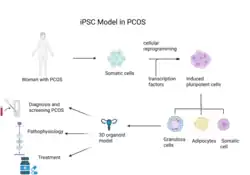

Stem cell models

Human embryonic stem cells (hESCs) derived from the inner cell mass of blastocyst-stage embryos of women with PCOS have shown abnormal lipid metabolism, consistent with the pathophysiology of the disease.[122] When the hESCs are differentiated into adipocytes, gene expression data from these fat cells reveal a downregulation or a decrease in genes linked to glucose, lipid, and steroid metabolism.[123]

As of 2024 studies have successfully developed in vitro PCOS disease models through Induced pluripotent stem cell technology (iPSC).[122] Similar to hESCs, iPSC cells can be derived from patients and can differentiate into various cell types. Using adult somatic cells, iPSCs can reprogram the cells into a pluripotent state, which can then be specified to replicate PCOS-like traits. Furthermore, 3D “organoid” models of female reproductive tissue, such as the uterus and ovaries, produced from iPSCs, present a powerful way to stimulate the development of reproductive disorders such as PCOS in vitro.[122]

Although not widely used, some researchers have explored the use of this biotechnology to model PCOS. One study that characterized the link between obesity and PCOS reprogrammed PCOS-derived urine epithelial cells into adipocytes and found that iPSC lines had greater glucose consumption along with lower insulin response compared to controls.[124] These are results consistent with symptoms of the disease. Studies on iPSCs have also contributed significantly to understanding the behavior of ovarian granulosa cells, which maintain follicular development and secrete steroid hormones.[125] The transcriptome data from the PCOS-derived iPSCs indicate dysfunctions in folliculogenesis and disruptions in the oocyte microenvironment.

Current growing data shows a strong association between mitochondrial malfunction and PCOS. iPSCs from PCOS patients have provided some evidence of impairments in glycolytic and mitochondrial functions.[122] These cells exhibited a higher number of copies of mitochondrial DNA compared to the control. This may support the idea that mitochondrial biosynthesis is elevated in these patients as a compensatory response to the aberrations seen in the metabolic processes.[122]